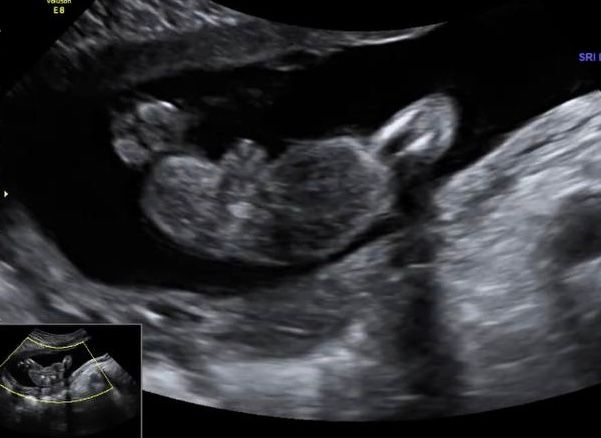

Little Koldynia, вообще нет,мне на первом ,втором говорили мальчик.Увидели девочку только на 3 скрининге.Вот фото 1,2 скрининга.А родила девочку по итогу ))) Изображение Изображение

27.10.2024

Весна, внизу это первый,а вверху второй.Да девочка родилась )

29.10.2024